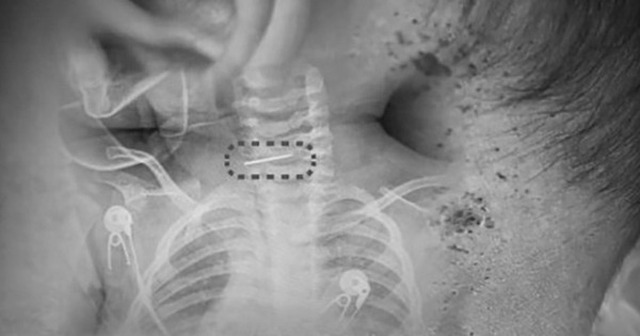

Tiếp nhận bệnh nhi trong tình trạng sốt cao, các bác sĩ phát hiện bé có nhiều vết kim đâm khắp cơ thể. Ngoài ra còn có một cây kim khâu giày gãy đôi, mắc kẹt sâu trong đốt sống cổ.

Theo tờ South China Morning Post (SCMP), người phụ nữ tên Dao đã dùng kim khâu giày đâm vào cổ đứa trẻ, khiến kim bị gãy và găm vào đốt sống cổ.

Bé trai bị sốt và co giật, bác sĩ phát hiện ra điều đáng sợ- Ảnh 1.

Bé trai bị nhiều vết kim đâm khắp cơ thể. Ảnh: Red Star News

Bác sĩ Sui cho biết ca phẫu thuật gặp nhiều khó khăn do cha mẹ không xác định được hình dạng chính xác của cây kim, cũng như việc kim có ngạnh hay không. Việc rút kim sai hướng có thể khiến đầu kim móc vào các mô khác và gây tổn thương nghiêm trọng.